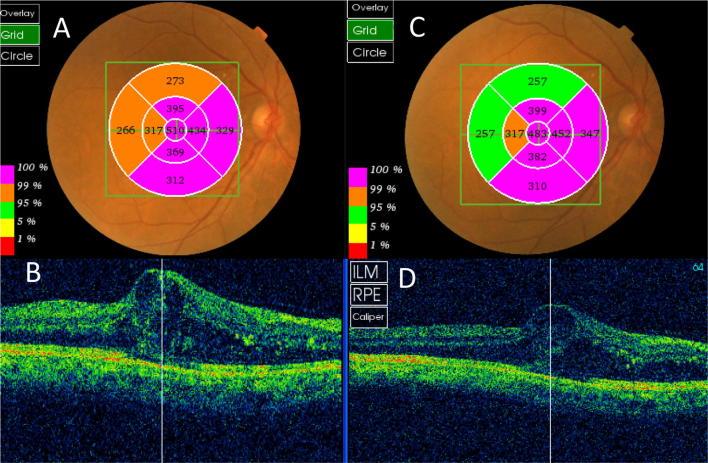

Fifty eyes with persistent DME were randomly allocated to intravitreal injection of 500 µg/0.1 ml of diclofenac ( = 20) or 1.25 mg/0.05 mL of bevacizumab ( = 20) or to non-treatment (10 eyes). Preoperative and postoperative visual acuity, central, paracentral macular thickness and intraocular pressure (IOP) were recorded and compared between the three groups up to 4 weeks.

Diclofenac and bevacizumab groups showed statistically significant reduction in central and paracentral macular thickness (diclofenac:  = 0.006, 0.02 and bevacizumab:  = 0.02, 0.01), without statistically significant difference between the two groups. The two groups showed no statistically significant difference in mean visual acuity or mean line improvement. Mean visual acuity improvement didn't reach statistical significance in either group. Diclofenac group showed statistically significant reduced IOP ( = 0.02). Control eyes did not show any change in mean visual acuity, macular thickness or IOP.

将50只患有持续性糖尿病黄斑水肿的眼睛随机分为三组,分别接受玻璃体内注射500μg/0.1ml双氯芬酸(n = 20)、1.25mg/0.05ml贝伐单抗(n = 20)或不进行治疗(10只眼)。记录术前和术后的视力、黄斑中心和旁中心厚度以及眼压(IOP),并在三组之间比较长达4周的数据。

双氯芬酸组和贝伐单抗组的黄斑中心和旁中心厚度均有统计学意义的降低(双氯芬酸组:P = 0.006,0.02;贝伐单抗组:P = 0.02,0.01),两组之间无统计学意义的差异。两组在平均视力或平均视力改善行数方面无统计学意义的差异。两组的平均视力改善均未达到统计学意义。双氯芬酸组的眼压有统计学意义的降低(P = 0.02)。对照组的平均视力、黄斑厚度或眼压均无变化。